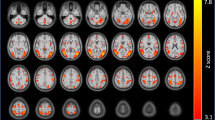

The IPN is divided into distinct sub-regions including rostral, intermediate, lateral and central (IPR, IPI, IPL and IPC, respectively)20. We challenged nicotine-dependent and nicotine-naive mice with mecamylamine (3 mg kg−1, intraperitoneal (i.p.)). Brains were collected 90 min post-injection, sliced and immunolabeled with c-Fos34, a marker of neuronal activation (Fig. 3a). Previously we demonstrated that activation of GABAergic neurons within the IPR triggers somatic but not affective symptoms22. Thus, we focused analysis on the ventral portion of the IPN containing the IPI, IPL and IPC. In chronic, nicotine-treated mice, mecamylamine activated a discrete population of neurons located within the IPI (Fig. 3a). To test the hypothesis that activation was mediated by CRF1 receptors, we preinjected control and nicotine-treated mice with antalarmin (10 mg kg−1, i.p.)35 and counted the number of c-Fos-immunopositive neurons within the IPI. Two-way ANOVA revealed a significant main effect of chronic treatment (F1,12=27.25, P=0.0002), preinjection (F1,12=16.25, P=0.0017) and a significant interaction (F1,12=5.783, P=0.0332). Mecamylamine significantly increased the number of c-Fos immunopositive neurons within the IPI of chronic nicotine-treated animals compared with control animals (Fig. 3b). In addition, antalarmin preinjection significantly reduced the number of c-Fos immunopositive neurons in the IPI during mecamylamine-precipitated nicotine withdrawal (Fig. 3b). As with IPN infusion of antalarmin, systemic delivery of antalarmin reduced anxiety-like behaviour in mice undergoing mecamylamine-precipitated nicotine withdrawal (Supplementary Fig. 4). We next tested whether neurons within the IPI express the CRF1 receptor. We performed fluorescent in situ hybridization (FISH) to detect CRF1 receptor mRNA in the IPN. Interestingly, CRF1 receptor mRNA is primarily localized to the IPI of the ventral IPN (Fig. 3c). To determine if CRF activates these neurons, we infused CRF into the IPN and combined FISH for visualization of CRF1 receptor mRNA expression with immunohistochemistry to detect c-Fos induction in the IPI. CRF infusion induced c-Fos expression specifically in the IPI. CRF1 receptor mRNA was also detected in the majority of c-Fos immunopositive neurons of the IPI (Fig. 3d). Finally, we confirmed that CRF1 receptor gene expression was upregulated in nicotine-dependent, compared to nicotine-naive, mice, specifically in laser-dissected ventral IPN (Table 1). Together, these data indicate that CRF activates IPI neurons through CRF1 receptor signalling and this signalling is upregulated with chronic nicotine exposure.

(a) Photomicrographs from coronal sections immunolabeled for c-Fos (green). Sections are taken from control or chronic nicotine-treated mice given i.p. injections of saline, mecamylamine (Mec, 3 mg kg−1) or antalarmin (Ant, 10 mg kg−1) before mecamylamine as indicated in the left-hand column. IPN sub-regions are indicated by dotted lines. (b) Each bar graph represents the average total number of c-Fos(+) IPI neurons after a mecamylamine i.p. injection or an injection of antalarmin 15 min before mecamylamine in control-treated (n=4 mice per treatment, 16 slices per mouse) or chronic nicotine-treated mice (n=3 and 5 mice per treatment, 16 slices per mouse). (c) Photomicrograph from representative coronal sections after FISH with a control (left) or CRF1 receptor probe. Note a robust CRF1 receptor signal is predominantly localized to the IPI sub-region of the IPN. (d) Photomicrograph of coronal sections from chronic nicotine-treated mice given a CRF infusion (300 ng) into the IPN. Sections are double-labelled for CRF1 receptor mRNA (using FISH, red) and c-Fos protein (using immunohistochemistry, green). Merged sections imaged at 10 × magnification are shown (middle). Scale bar: 200 μm. Outside sections shown at 63 × magnification illustrate localization of c-Fos in CRF1 receptor-expressing IPI neurons. Scale bar: 20 μm. Data are expressed as mean±s.e.m. Two-way ANOVA, Bonferroni post hoc test. ***P<0.001 compared with saline preinjection within groups. ^^P<0.01 chronic nicotine-treated compared with control-treated mice.